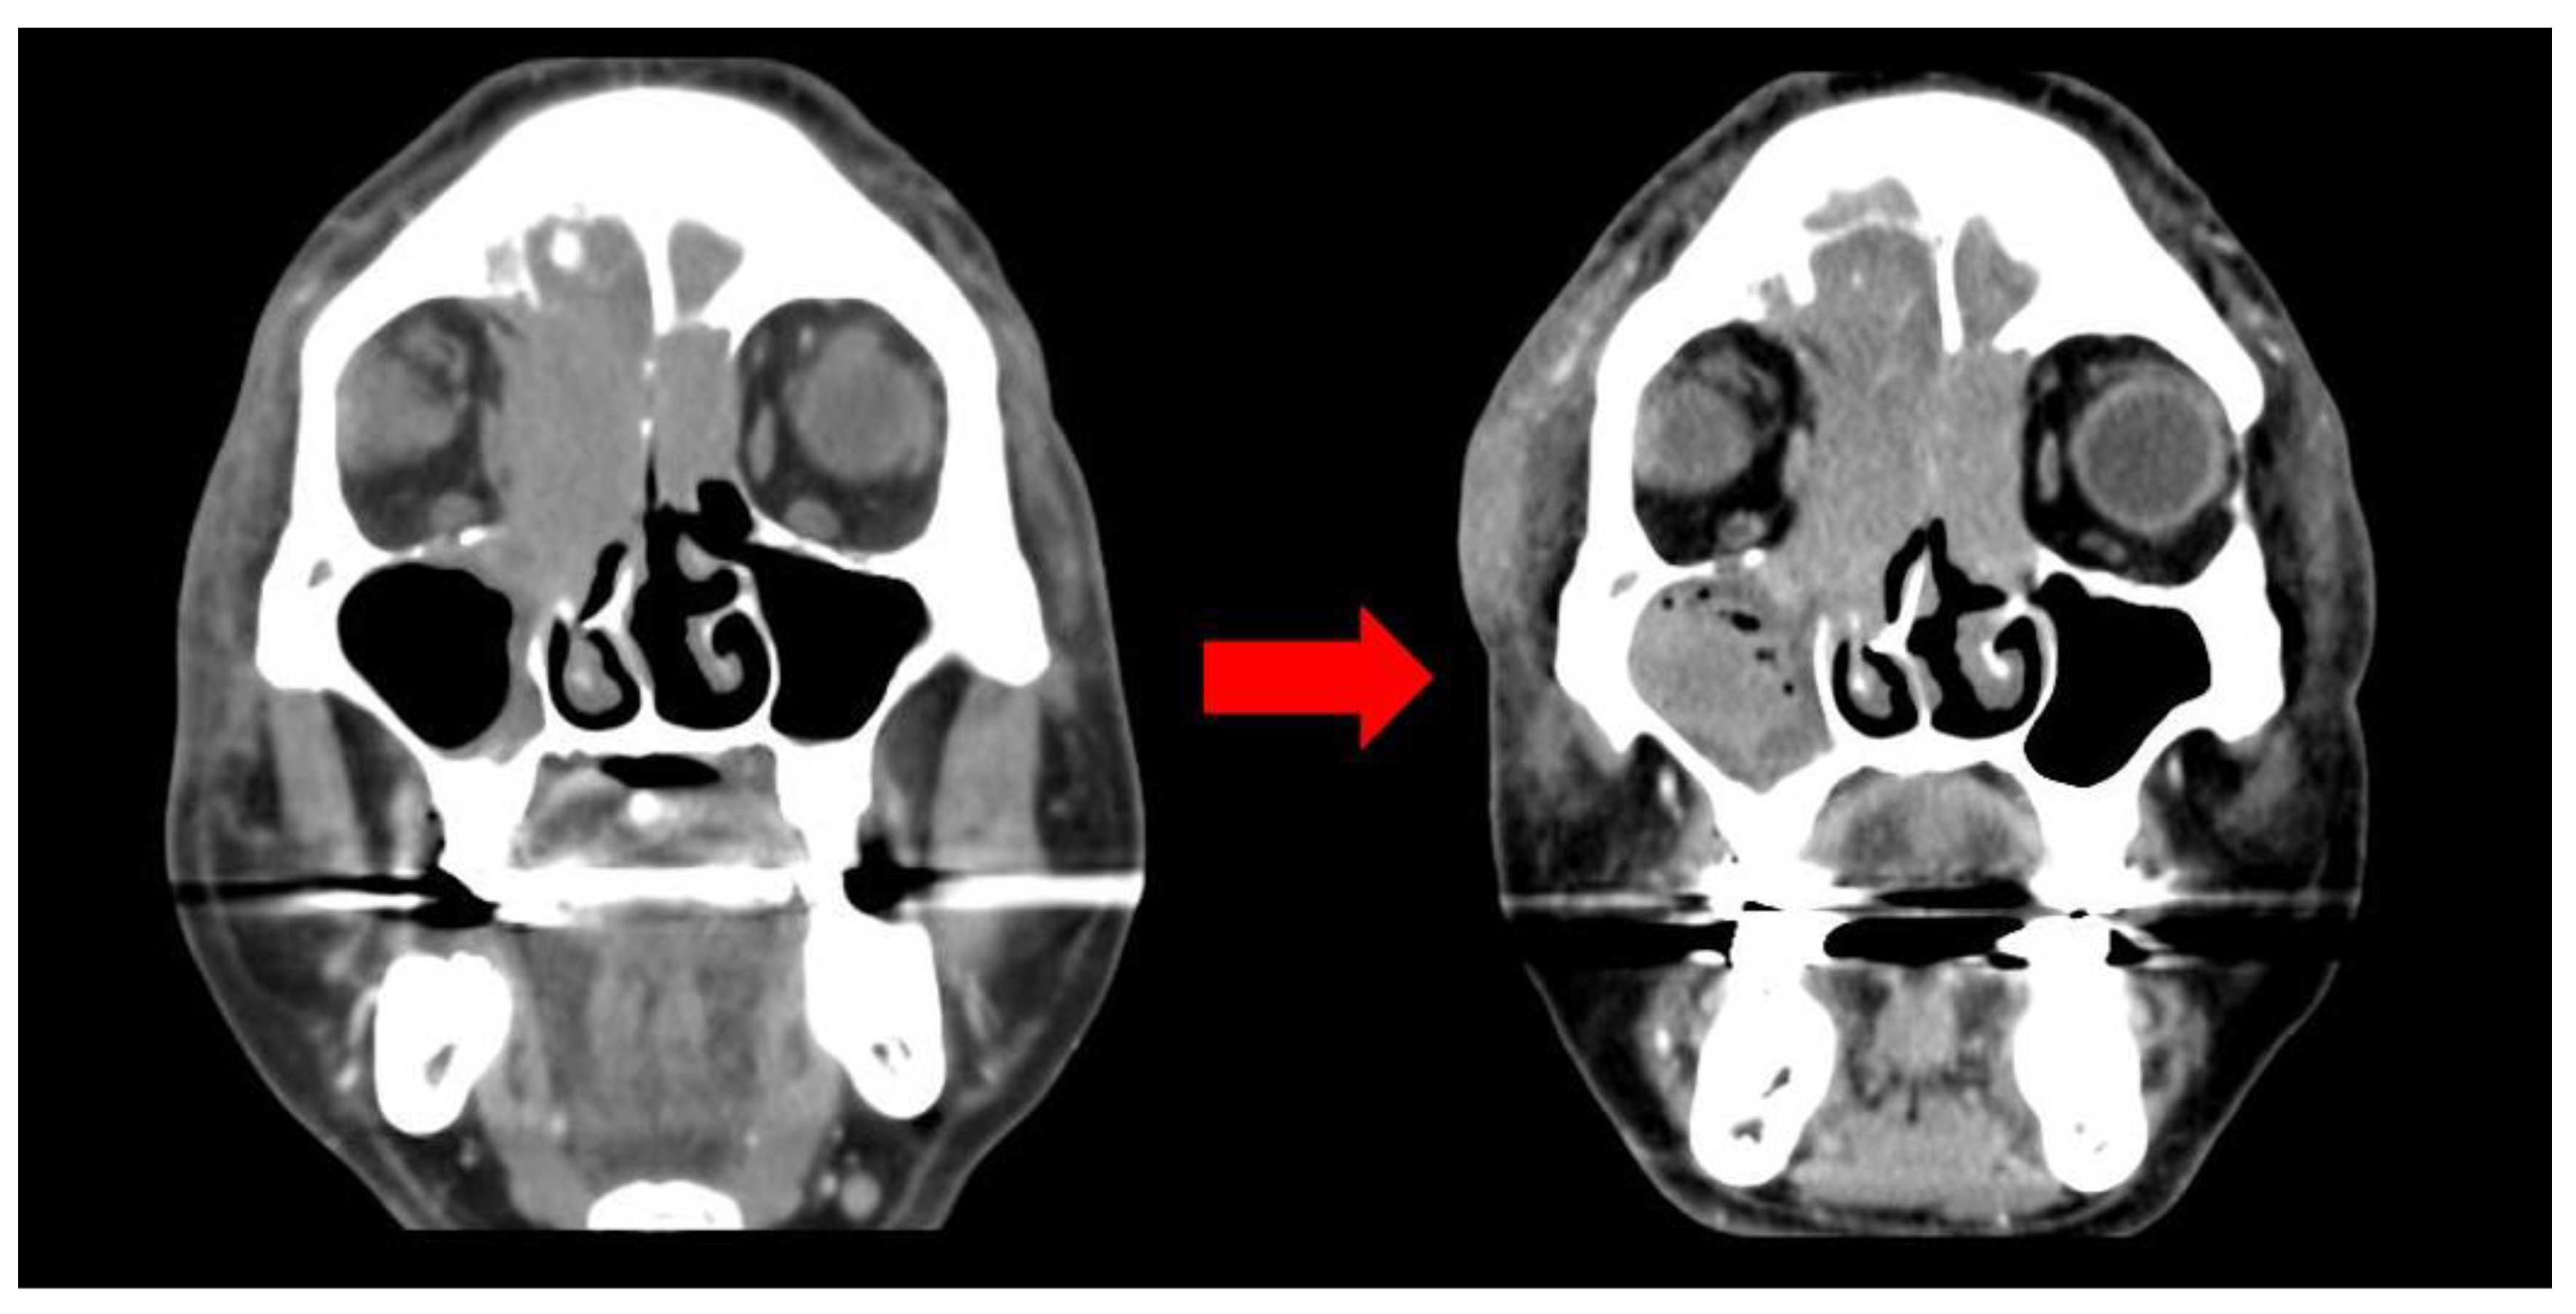

2. Case Report